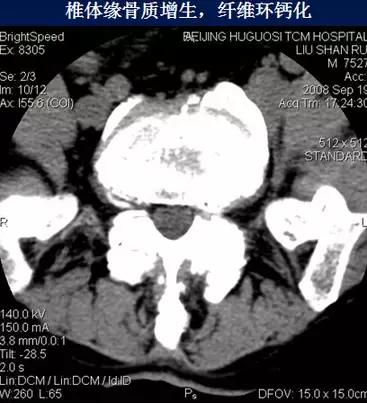

一、椎间盘退行性变

4、纤维环钙化